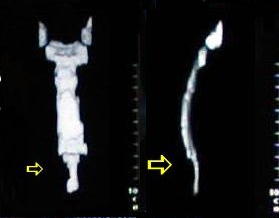

Reconstrucción Osea Tomográfica

• El esternón frente y lateral:

• observe la convexidad del cuerpo esternal y la concavidad que ocasiona el desplazamiento anterior del pronunciado apéndice sifoides.

• Las estructuras mediastinales se alojan en un tórax que ha disminuido su diámetro antero-posterior por la depresión esternal y la marcada concavidad de la columna dorsal.

• La reconstrucción ósea torácica tomográfica demuestra que las alteraciones presentes en el tórax están limitadas básicamente al defecto esternal.

• Los arcos cartilaginosos costales, causantes de los defectos del tórax están ausentes, en el proceso de reconstrucción tomográfica.

•  Procedimiento de estudio computarizado, mediante el cual las imágenes tomográficas son superpuestas con ayuda de un software especial y permite una proyección tridimensional de los elementos óseos, dando una imagen aspecto 3D, de volumen y distribución con alto contenido docente y demostrativo. el aporte de esta tecnica en esta patologia es unicamente con fines conceptuales demostrativos docentes.